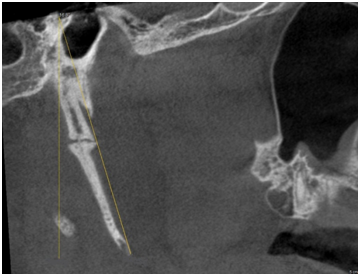

The morphology of SHC was recorded to evaluate the general structural appearance and the number of segments and was categorized into 3 types as single segment ossification, two segment ossification and three segment ossification (Figures 1‒3). The length was defined as the distance between the base of the SP and the tip of the ossified SHC. If there was segmental ossification of the SP, the distance was measured including the non-ossified parts (Figure 4). The antero posterior angle (APA) was defined as the angle made by the process with the perpendicular dropped from the lateral part of the external auditory meatus (Figure 5). The mediolateral angulation (MLA) was defined angle of intersection between the longitudinal axis of the SHC to the perpendicular dropped from the base of the process (Figure 6).

Figure 5 Shows measurement of Antero posterior angulation (APA).